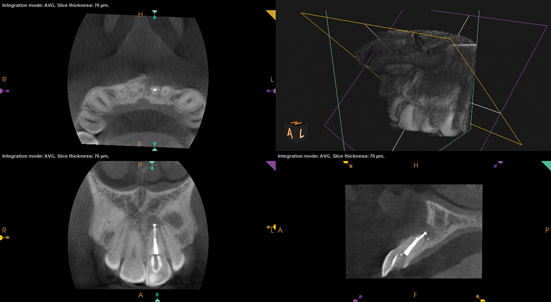

(9.) Preoperative radiograph of previously treated tooth No. 9, which received a diagnosis of acute apical abscess secondary to childhood trauma and recurrent endodontic pathology.

Figure 9

(10.) Posttreatment radiograph and cone-beam computed tomography (CBCT) scan following nonsurgical root canal re-treatment that resulted in incomplete resolution of symptoms in response to percussion and palpation.

Figure 10

(11.) Posttreatment radiograph and cone-beam computed tomography (CBCT) scan following nonsurgical root canal re-treatment that resulted in incomplete resolution of symptoms in response to percussion and palpation.

(12.) Postoperative radiograph after apical surgery was performed using MTA as an apical retrofilling material.

(13.) Normal healing was noted clinically and radiographically at the 6-month follow-up appointment.